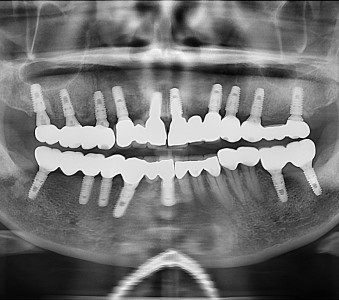

오스템 임플란트 프리미엄 BA 등급 사용

같은 오스템이라도 등급이 다릅니다. 더 빠른 골유착을 위해 프리미엄 등급을 사용합니다.

정확성 높은 치료의 시작 디지털 정밀진단 시스템

3D 디지털 데이터 기반으로 정확성 높고 정교한 치료가 가능합니다.

결과로 증명합니다.

국제모아치과의

실제 임상 증례